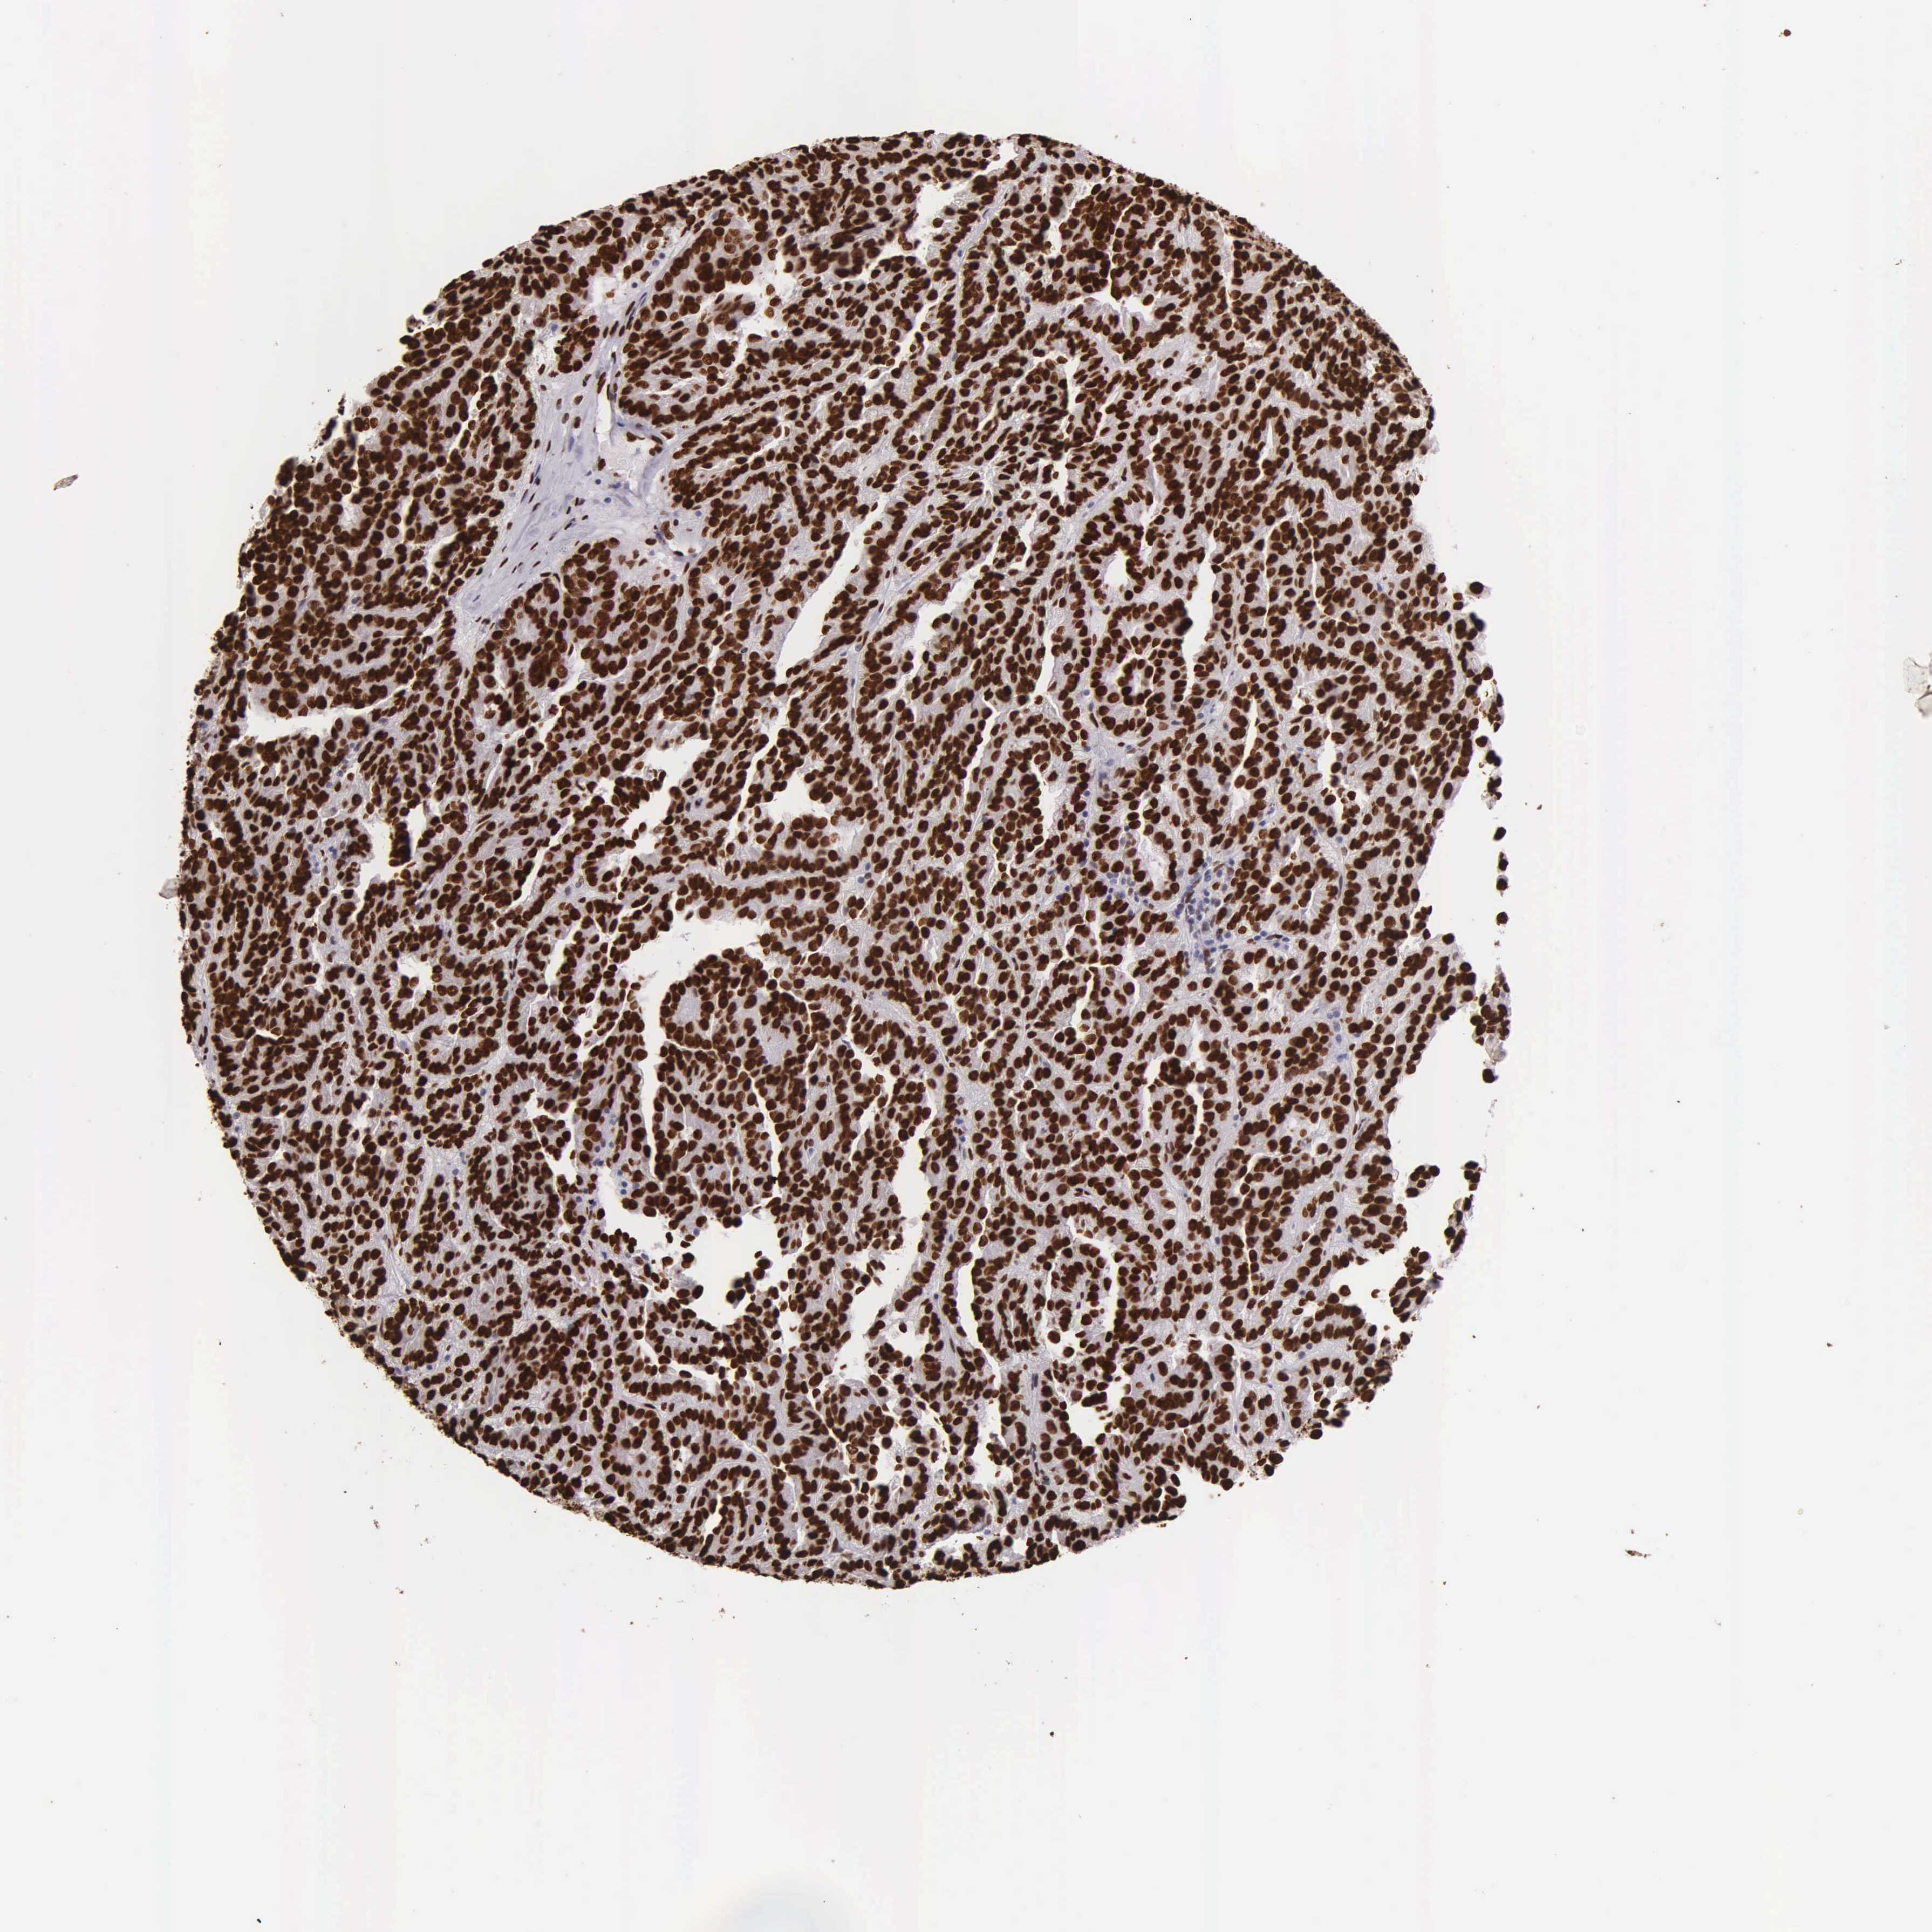

CANCER RENAL CANCER Show tissue menu

KICH TCGA KIRC TCGA KIRC VALIDATION KIRP TCGA PROTEIN RCC CPTAC PROTEIN EXPRESSION